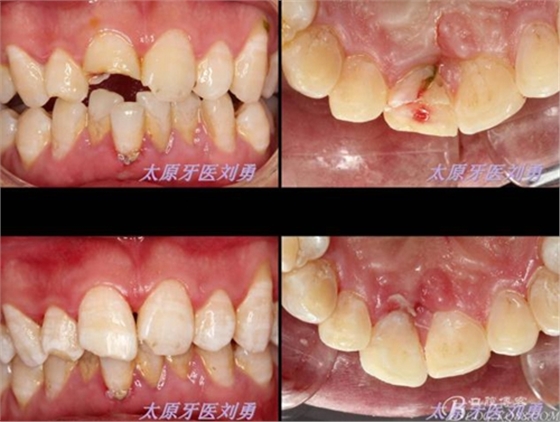

第二日復(fù)查,給予樹(shù)脂恢復(fù)A2A1B1切斷缺損。術(shù)后如下圖:

此病例純屬嘗試性操作,遠(yuǎn)期效果有待隨訪。目前已經(jīng)完成2月余,患者自述無(wú)任何不適。待后隨訪,再分享經(jīng)驗(yàn)與心得。